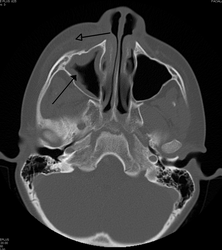

If the diagnosis is unclear, a CT scan may be done to rule out other possibilities.

Periorbital cellulitis must be differentiated from orbital cellulitis. In contrast to orbital cellulitis, periorbital cellulitis do not have bulging of the eye (proptosis), limited eye movement (ophthalmoplegia), pain on eye movement, or loss of vision.